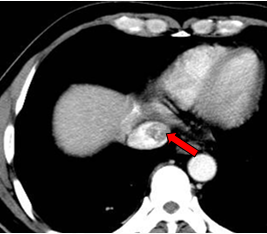

现病史:2011年01月4日于当地医院行PET/CT: 1. 肝左外叶肝癌并肝门区淋巴结转移,2. 下腔静脉及右心房结癌栓,考虑为”原发性肝癌“。

肝左叶巨块型肝癌(13.8cm×9.1cm),伴肝右后叶子灶,门静脉左支、肝左静脉及下腔静脉内癌栓。